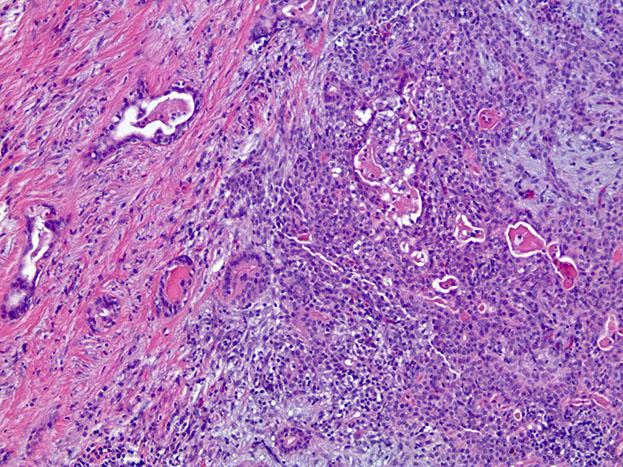

Adenoid Cystic Carcinoma

- aka cylindroma

~1/15 of all salivary gland tumors; seen in older women

- mostly (60%) seen in minor salivary glands, esp in the palate; (MC malignant tumor of minor salivary glands)

Have extensively invasive growth patterns, esp perineural invasion

Micro: Biphasic c ductal lining and ME cells with cribriform, tubular or solid pattern and hyaline material filling the spaces bwt tumors (stromal hyalinization [thick BM])

- usually contains at least some cribriform nests (Swiss cheese) filled c myxoid (blue goo), but may not be present on small bx

- tumor cells should not have intracytoplasmic mucin (found in MEC) - mucin is secreted into pseudocysts - also shound not have squamous metaplasia

- considered high-grade if >30% has solid growth pattern - has calcification / comedonecrosis in high grade

Adenoid cystic ca

High grade adenoid cystic ca c comedo necrosis